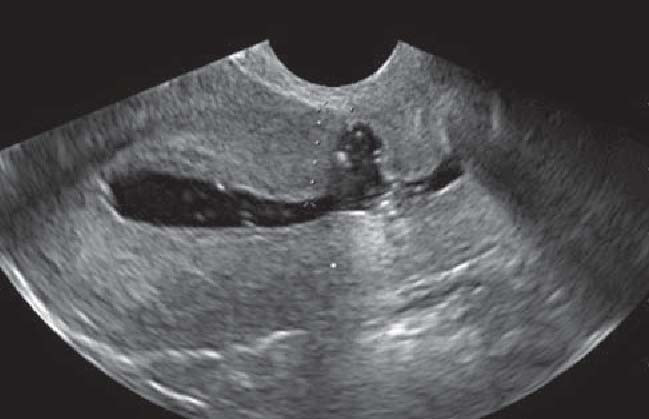

Niche esetén a hüvelyi ultrahangon egy fekete háromszöget látunk a belső méhszáj felett. De nem kizárólag ez az oda nem illő „kitüremkedés” okozhatja a problémákat. A heg felett elvékonyodik a méh izomrétege és a méhüreg felől kóros nyálkahártya jelenik meg, amely a menstruációs vér megrekedéséhez vezethet. A nyálkahártyán található erek ezen felül folyadékot szűrnek át, ami feltételezhetően a vérzészavar legfőbb oka, de megváltoztathatja a méhüreg miliőjét is, ami egyes szakmai vélemények szerint csökkent termékenységet vagy másodlagos meddőséget okoz. Az elváltozás szerencsére kezelhető műtéti úton. A heget borító izomréteg vastagságától függően méhtükrözés vagy hastükrözés segíthet.